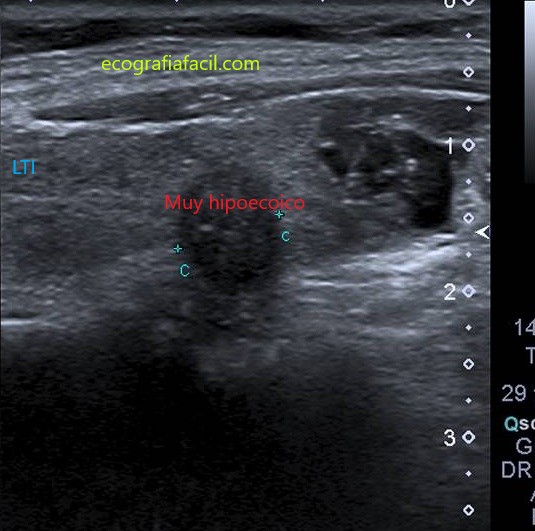

HIPOECOICO+:

Para definir la ecogenicidad de los nódulos isoecoicos se compara con el parénquima de la glándula tiroidea y para nódulos hipoecoico, hiperecoico o muy hiperecoico conviene compararla con la del músculo adyacente (músculo esternocleidomastoideo).

ECOGENICIDAD: Muy hipoecoica          3